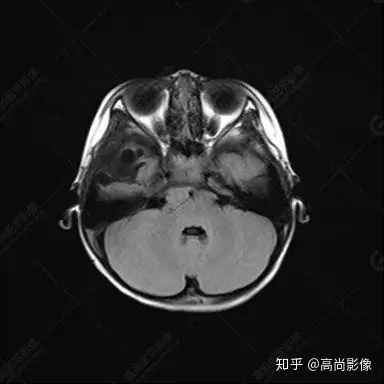

右側(cè)顳葉腫瘤切除術(shù)后(具體不詳):右側(cè)顳部骨質(zhì)不連續(xù)呈術(shù)后改變,右側(cè)顳葉術(shù)區(qū)見片狀長T1長T2信號(hào)影,F(xiàn)LAIR呈低信號(hào);術(shù)區(qū)后方右側(cè)顳枕葉見一巨大占位性病變影,邊界欠清,大小約6.2×5.8×4.3cm(前后×左右×上下),信號(hào)不均勻,T1WI呈等稍低信號(hào)間雜少許高信號(hào),T2WI呈高稍低混雜信號(hào),DWI示部分病灶彌散受限,相應(yīng)ADC圖減低,磁敏感序列見部分呈極低信號(hào),增強(qiáng)掃描可見明顯不均勻強(qiáng)化,鄰近硬腦膜及小腦幕增厚并明顯強(qiáng)化;另延髓右前方及右側(cè)橋小腦角區(qū)見一不規(guī)則形異常信號(hào)影,大小約3.2×1.3×3.7cm(左右×前后×上下),呈長T1稍長T2信號(hào),F(xiàn)LAIR呈等信號(hào),DWI未見受限,增強(qiáng)后明顯均勻強(qiáng)化,鄰近腦膜明顯強(qiáng)化。鄰近腦實(shí)質(zhì)及右側(cè)顳角明顯受壓;左側(cè)大腦半球未見局灶性信號(hào)異常,中線結(jié)構(gòu)稍左移。

右側(cè)顳葉腫瘤切除術(shù)后:現(xiàn)術(shù)區(qū)后方右側(cè)顳枕葉及延髓右前方占位,右側(cè)顳枕部硬腦膜及小腦幕明顯強(qiáng)化,結(jié)合既往影像資料,考慮為胚胎源性惡性腫瘤,如非典型畸胎樣/橫紋肌樣瘤(AT/RT)或原始神經(jīng)外胚層腫瘤(PNET)。